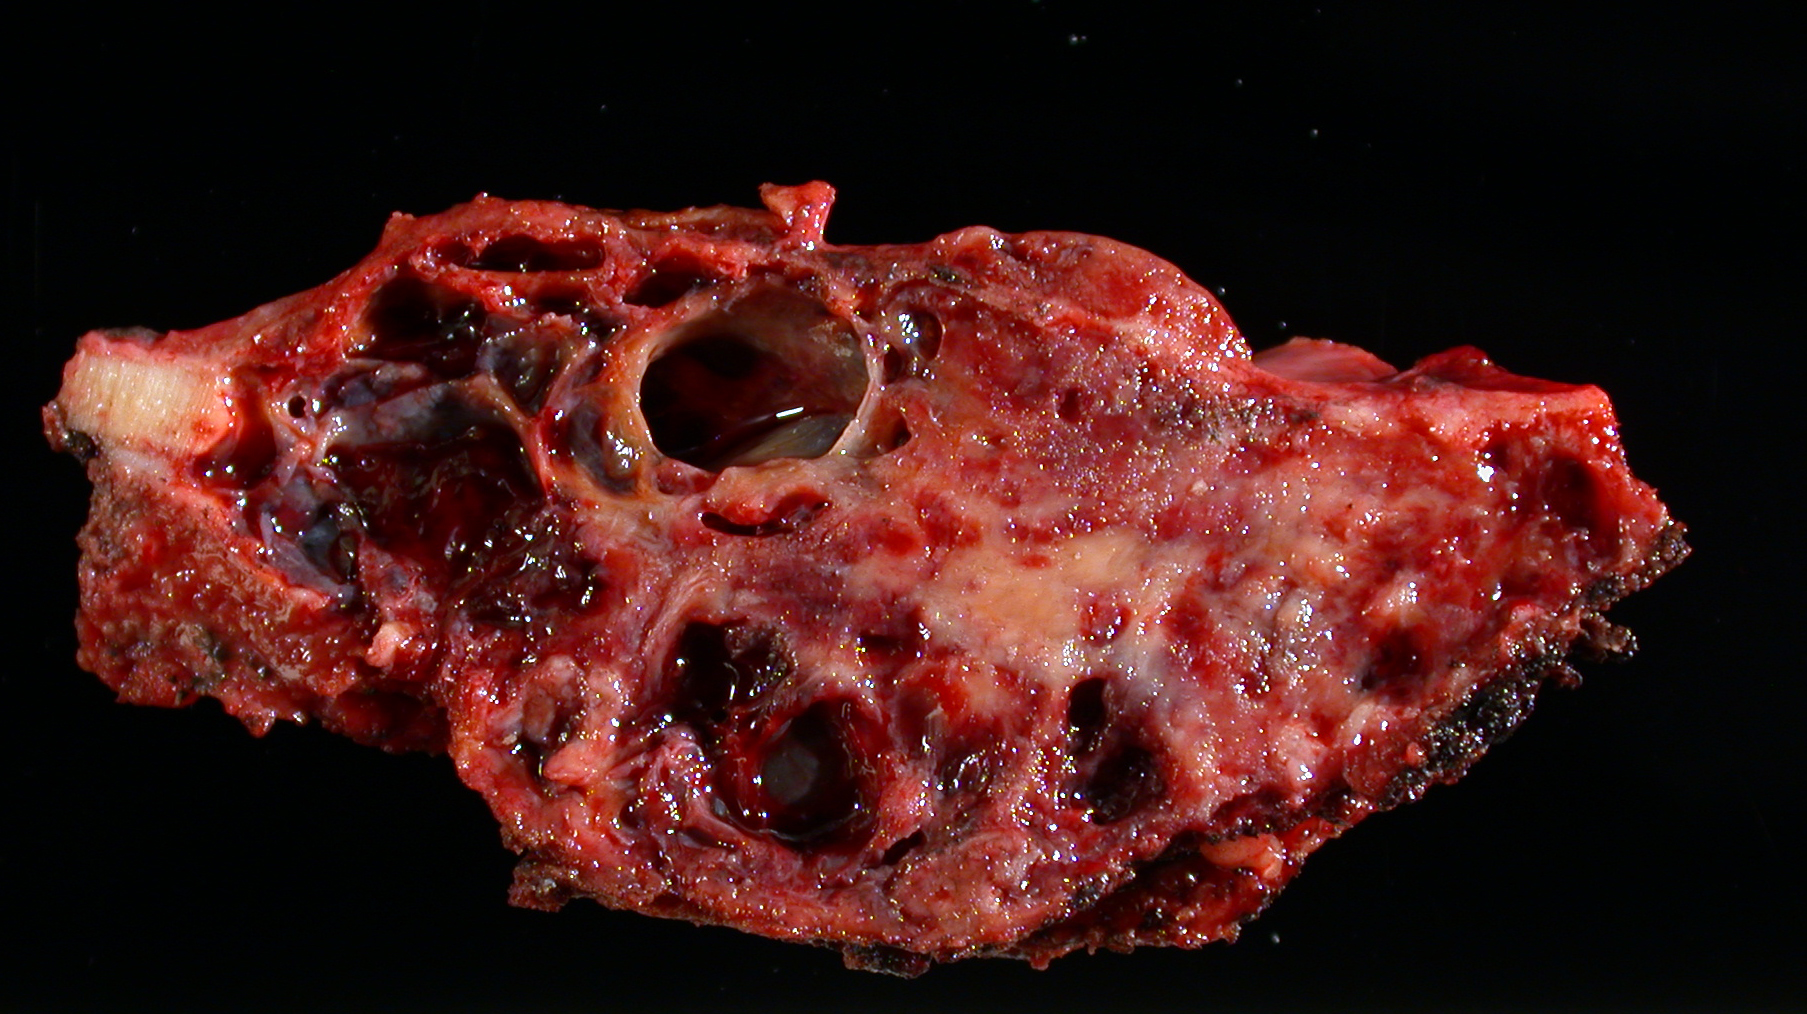

Gross description

- Spongy, multiloculated, hemorrhagic lesion

- Variable size

- Irregular, sharply demarcated borders with thin shell of reactive bone

- Variable amount of solid component